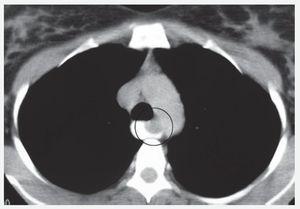

Mujer de 34 años sin antecedentes personales patológicos, quien consulta con historia de 3 meses de evolución de disfagia progresiva. Estudio baritado esofágico reveló compresión extrínseca en tercio medio (Imagen 1). La endoscopia alta mostró una lesión que ocluía 50% de la luz esofágica con mucosa intacta. La tomografía axial computada con contraste esofágico reveló una lesión intramural, no adherida a planos adyacentes a nivel de la pared esofágica lateral derecha en el tercio medio, cercano al cayado aórtico (Imagen 2). A la paciente se le realizó enucleación toracoscópica con abordaje lateral derecho de tumoración esofágica en tercio medio sin complicaciones (Fotos 1 y 2). El informe histopatológico reportó GIST (Gastrointestinal Stromal Tumor) esofágico CD117 (+). Estudio contrastado de control sin estrecheces ni escape. Fue dada de alta al cuarto día posoperatorio.

Imagen 2. TAC de esófago con contraste. Lesión intramural.